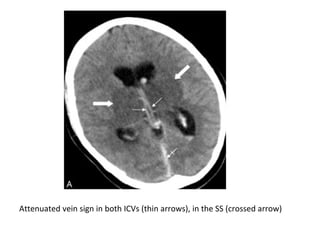

- Cord sign : is defined as a homogeneous ,

hyperattenuated appearance of thrombosed

venous sinuses , the hyperattenuated

appearance of the affected veins often being

named (the attenuated vein sign)

Attenuated vein sign in both ICVs (thin arrows), in the SS (crossed arrow)

Attenuated vein sign in both ICVs (thin arrows) , in the SS (crossed arrow) as

well as bilateral edema in the thalami and in the putamen (thick arrows)